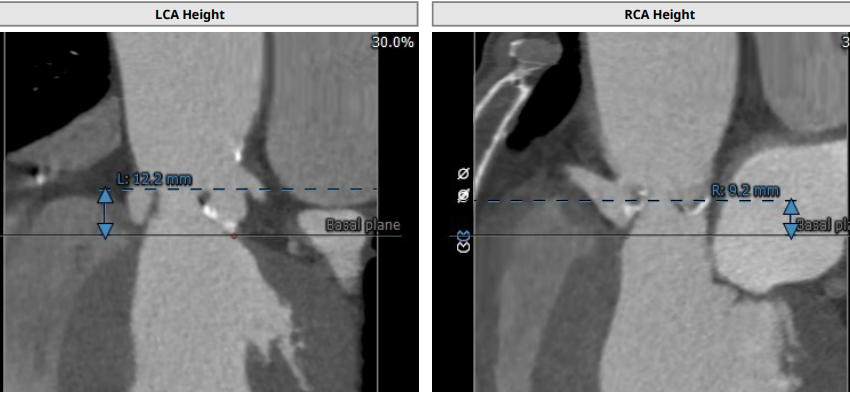

术前CT

中度钙化四叶瓣,瓣环面积:418mm²,流出道面积:476mm²,左冠开口高度:12.2mm,右冠开口高度:9.2mm。